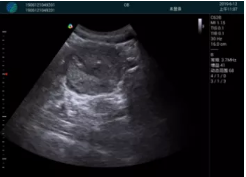

腺體內(nèi)部清晰顯示一低回聲塊影,形態(tài)不規(guī)則,邊界模糊,邊緣呈毛刺狀,內(nèi)部見砂礫樣鈣化

M20引導(dǎo)下穿刺活檢術(shù)

M20引導(dǎo)下平面內(nèi)穿刺取出的腫塊組織